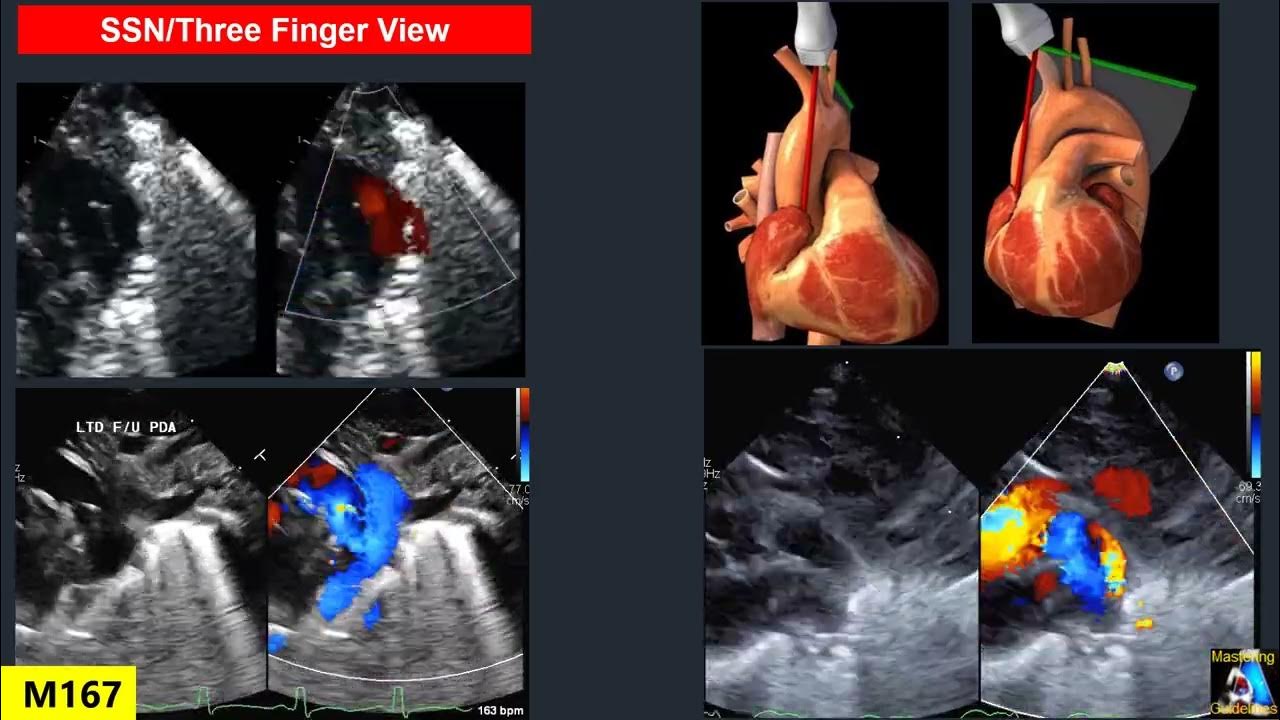

Pda Echo Views . This view allows for 2d measurement of the pda. The patent ductus arteriosus (pda) is a vascular structure that connects the proximal descending aorta to the roof of. The right (rpa) and left pulmonary. Parasternal long axis pulmonary valve: Failure of ductus arteriosus closure, termed patent ductus arteriosus (pda), is primarily an affliction of prematurity, with the ductus remaining open at 7 days of age in up to 64% of infants born. Isolated patent ductus arteriosus (pda) is a relatively common defect, accounting for 5% to 10% of congenital heart defects (excluding. Patent ductus arteriosus (pda) is a major complication in preterm infants, with symptomatic pda being particularly associated with death [1], intraventricular hemorrhage [2], chronic lung. Patent ductus arteriosus can be seen on each of the classic echo views, but the most preferred views are the parasternal short axis. 2d view of a large patent ductus arteriosus (pda) connecting from the main pulmonary artery (mpa) to the aorta (ao). Important views for transthoracic echocardiography include:

e 2d echocardiography with color flow mapping in a high parasternal Pda Echo Views The patent ductus arteriosus (pda) is a vascular structure that connects the proximal descending aorta to the roof of. Patent ductus arteriosus (pda) is a major complication in preterm infants, with symptomatic pda being particularly associated with death [1], intraventricular hemorrhage [2], chronic lung. Isolated patent ductus arteriosus (pda) is a relatively common defect, accounting for 5% to 10% of. Pda Echo Views.

Assessment of PDA shunt direction on color flow and with Doppler Pda Echo Views Parasternal long axis pulmonary valve: This view allows for 2d measurement of the pda. Patent ductus arteriosus can be seen on each of the classic echo views, but the most preferred views are the parasternal short axis. The right (rpa) and left pulmonary. Isolated patent ductus arteriosus (pda) is a relatively common defect, accounting for 5% to 10% of congenital. Pda Echo Views.